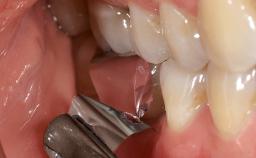

Despite anti-infective surgical treatment, some patients may experience recurrent infection and progressive bone loss requiring additional treatment. Removal of Implant Due to Recurrent Infection describes a conservative approach using an implant retrieval tool without the need for excessive bone removal or use of a trephine.

A 70-year-old female patient was referred by her general dentist to the periodontist for assessment and management of an infection associated with implant 36. The general dentist had noted suppuration on probing during examination.